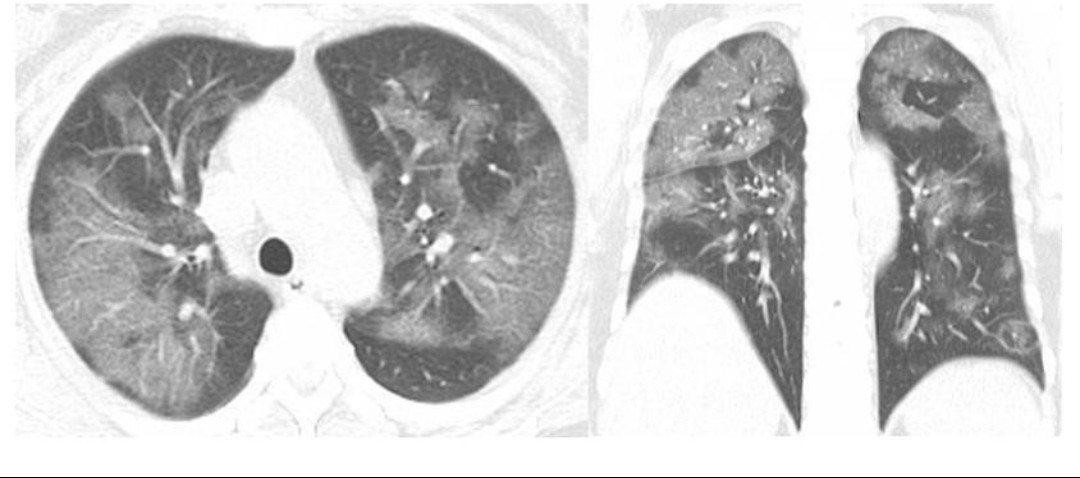

Визуализация и диагностика неинвазивного аспергиллеза с помощью КТ